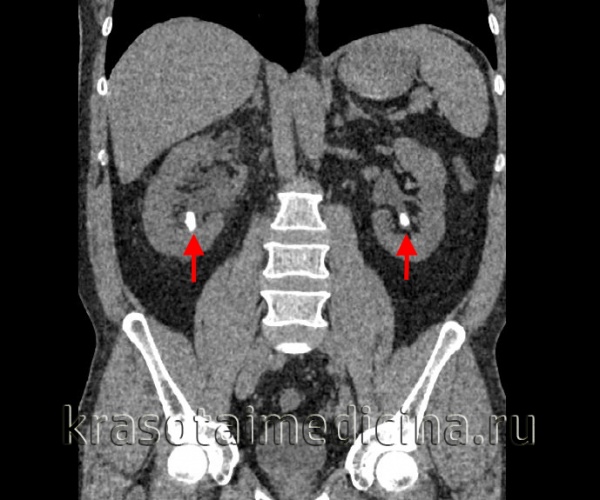

б) Спиральная компьютерная томография (КТ) без контрастирования позволяет эффективно диагностировать камни почек и мочеточников. К ее преимуществам относятся: отсутствие необходимости в применении контрастного вещества, быстрота выполнения и возможность выявления не только кальциевых, но также и уратных, и цистиновых камней.

- КТ почек. Компьютерная томография является "золотым стандартом" диагностики, поскольку позволяет увидеть конкременты любых размеров и плотности. При необходимости урологическое обследование дополняется радиоизотопной нефросцинтиграфией.

КТ ОБП и забрюшинного пространства. Плотные конкременты в нижних чашечках с обеих сторон. (фото Вишняков В.Н.)